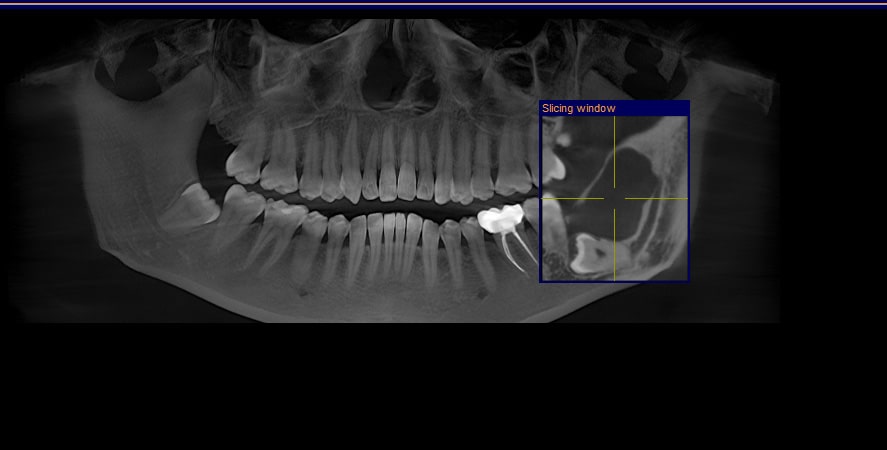

At Kamala Dental Super Speciality Hospital, Thiruvananthapuram, we utilize advanced Cone Beam Computed Tomography (CBCT) and 3D scanning technologies to obtain highly detailed images of your teeth, jaws, nerves, and surrounding structures. These cutting-edge tools empower our team to diagnose more accurately and plan treatments with greater precision - giving you safer, more predictable outcomes.

- Detailed, Clear Views: CBCT produces 3D images of bone anatomy, root canals, jaw joints, sinuses, and nerve pathways - far more informative than traditional 2D X-rays.

- Accurate Diagnosis: Detect hidden problems such as impacted teeth, root fractures, infections, and bone defects early.

- Diagnosis of root canal anatomy & complex endodontic cases

- State-of-the-Art Technology: We have the latest Dentsply Sirona Othophos SL 3D CBCT scanners and intraoral 3D imaging systems in-house.

- Expert Interpretation: Our experienced dentists and specialists analyze the scans for accurate diagnosis and implant or surgery planning.